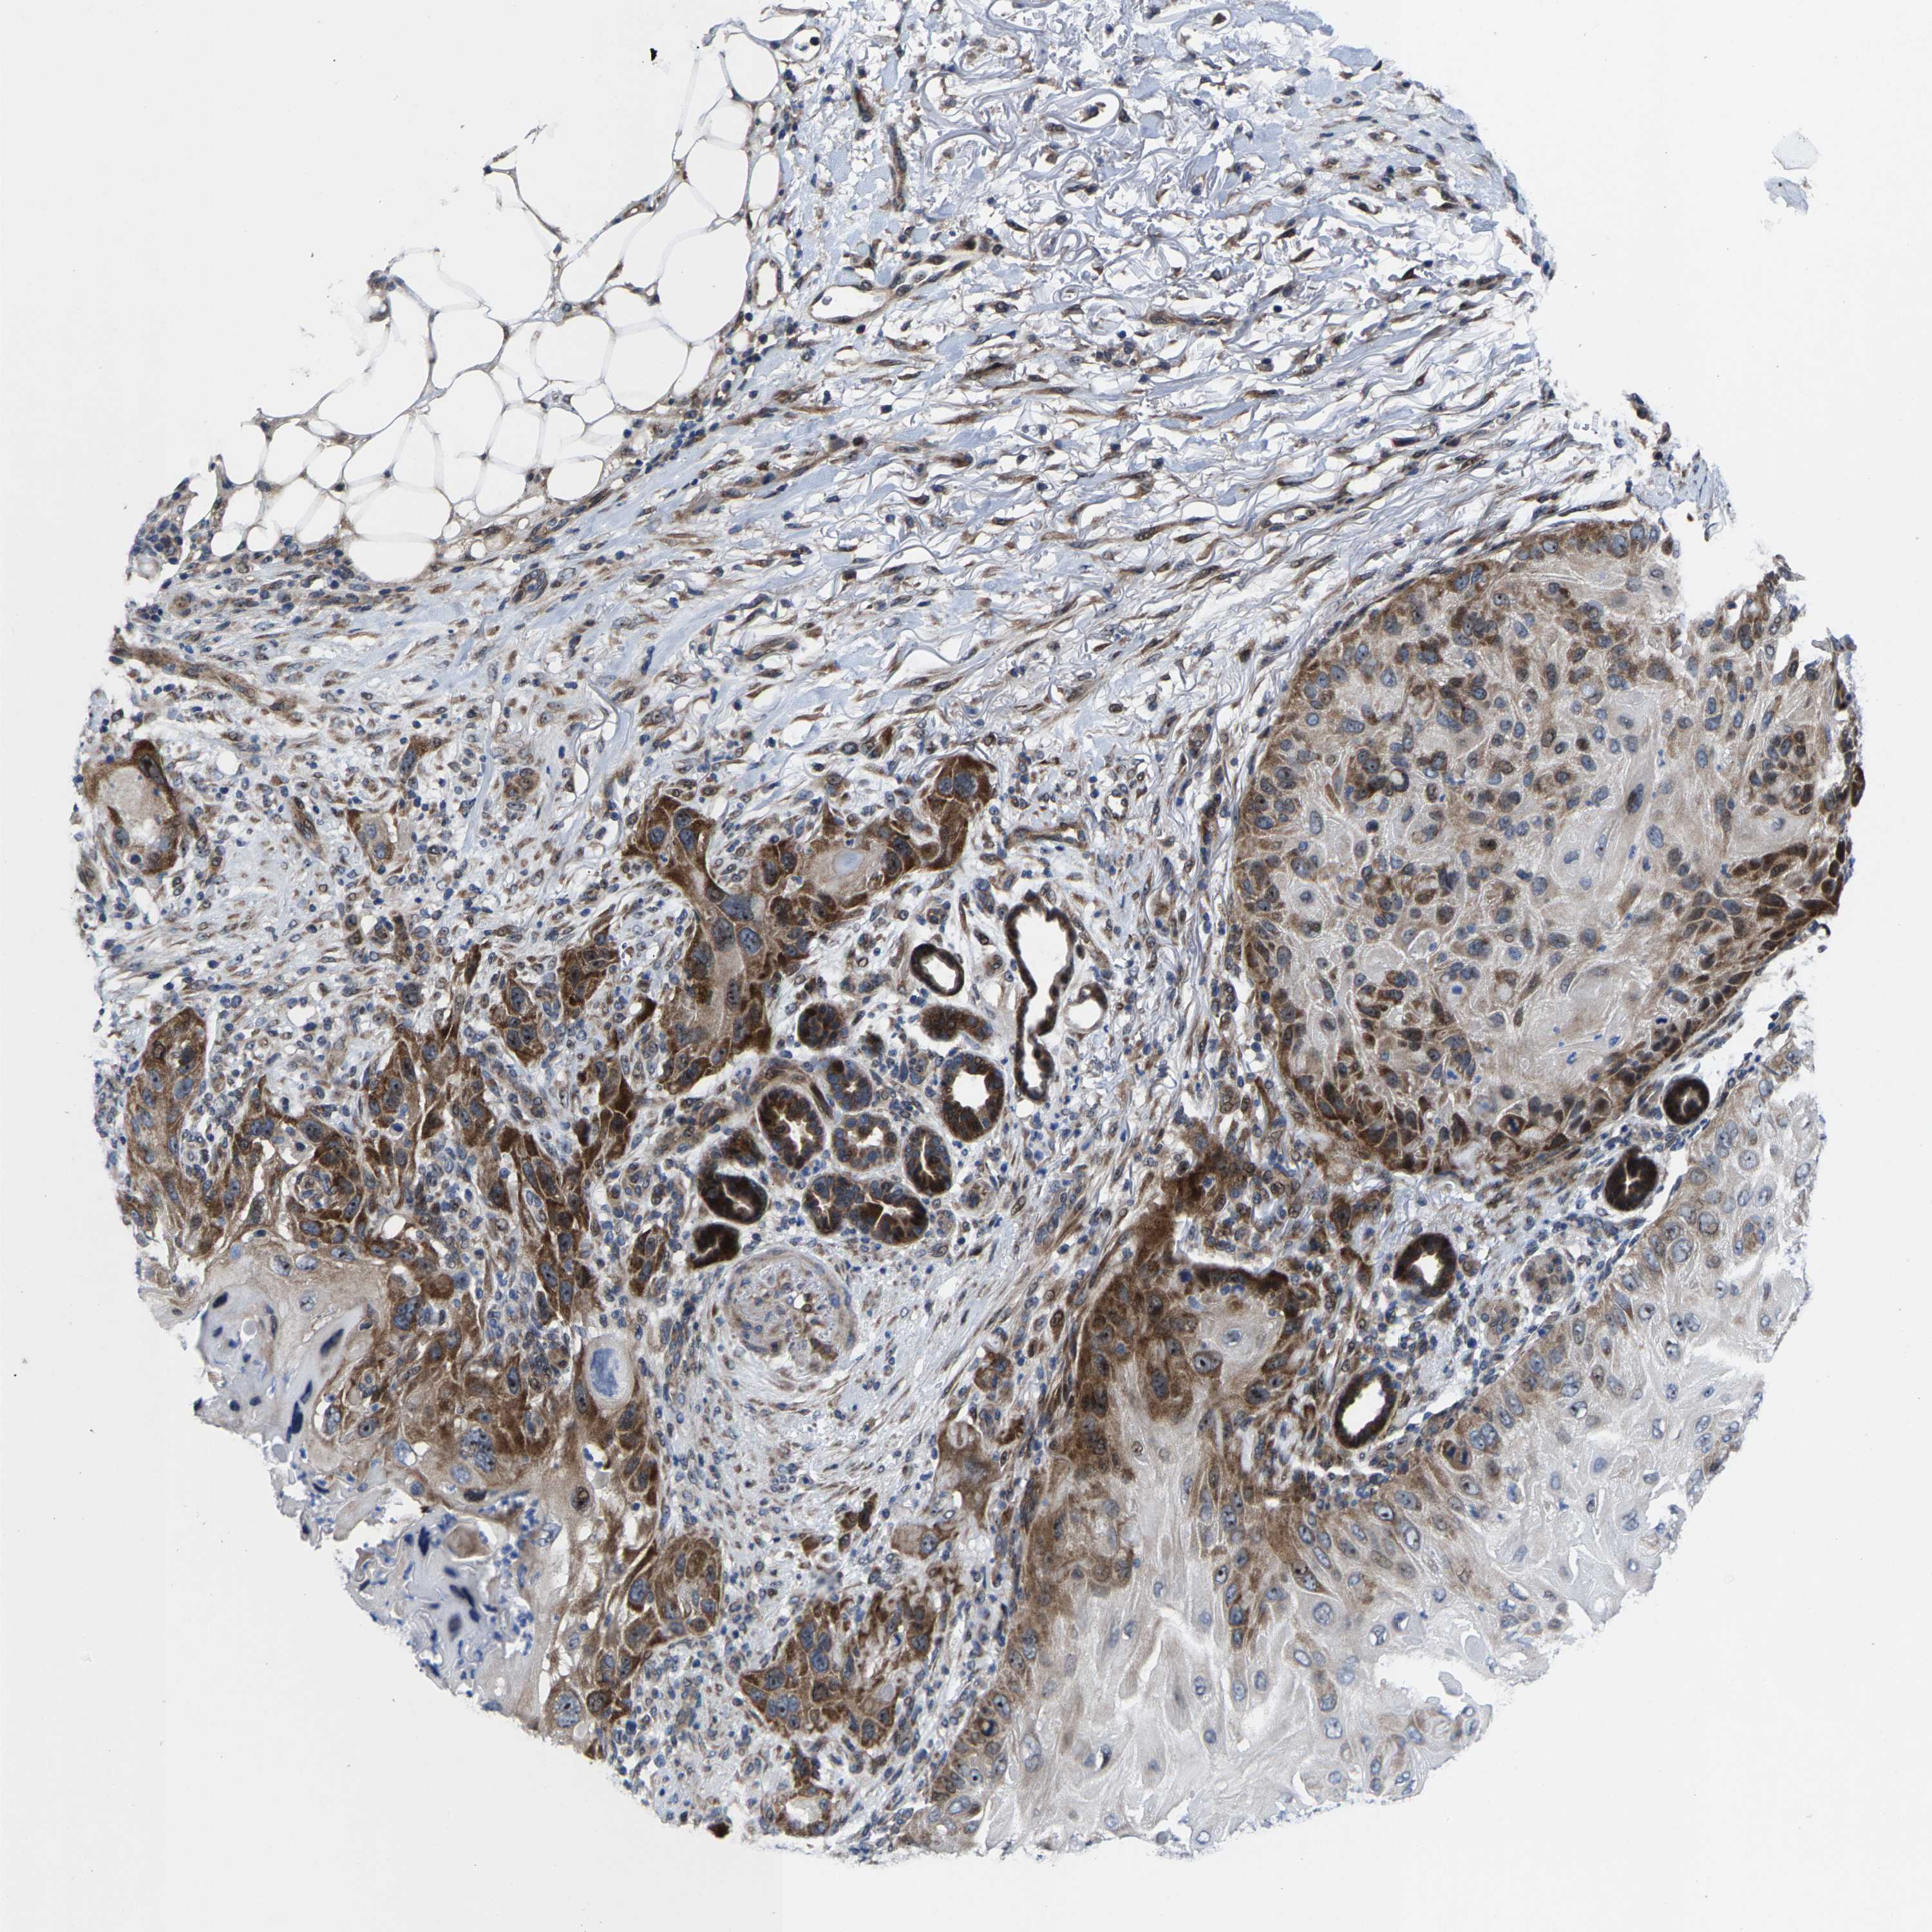

SKIN CANCER - Protein expressioni

A mouse-over function shows sample information and annotation data. Click on an image to view it in a full screen mode. Samples can be filtered based on level of antibody staining by selecting one or several of the following categories: high, medium, low and not detected. The assay and annotation is described here.

Antibody stainingi

Antibody staining in the annotated cell types in the current human tissue is reported as not detected, low, medium, or high, based on conventional immunohistochemistry profiling in selected tissues. This score is based on the combination of the staining intensity and fraction of stained cells.

Each image is clickable and will lead to virtual microscopy that enables deeper exploration of all samples and also displays staining intensity scores, fraction scores and subcellular localization as well as patient and tissue information for each sample.

Antibody HPA020965

Squamous cell carcinoma, NOS